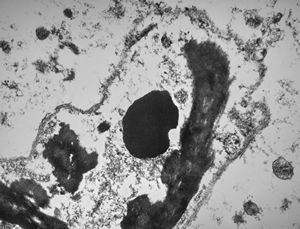

F,50y. | progressive multifocal leukoencephalopathy- viral particles in a glial cell

F,50y. | progressive multifocal leukoencephalopathy- viral particles in a glial cell

F,50y. | progressive multifocal leukoencephalopathy- viral particles in a glial cell